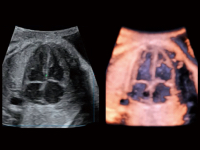

胎兒顱腦融合

時(shí)間空間相關(guān)成像

S-Fetus? 鳳眼(A4C切面)